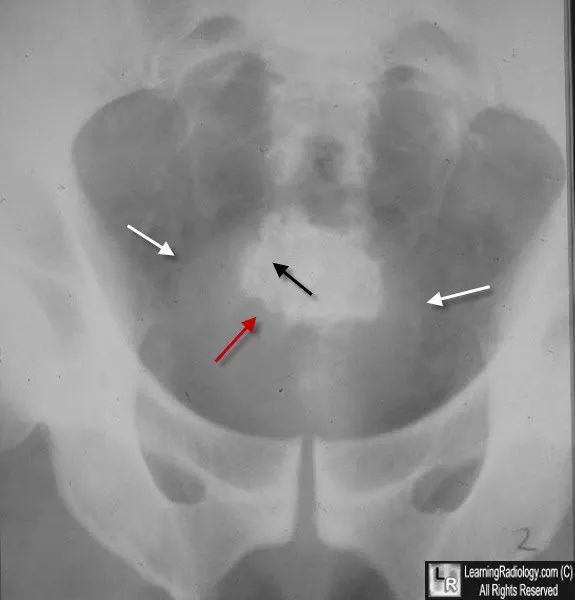

图2 Jackstone膀胱结石。骨盆X光片显示层状结石(黑色箭头显示稍致密的钙化层),膀胱软组织阴影内(白色箭头)有多个不规则边缘(红色箭头)。这些锯齿状边缘被认为是由于慢性出口梗阻,导致小梁形成,如良性前列腺增生(BPH)